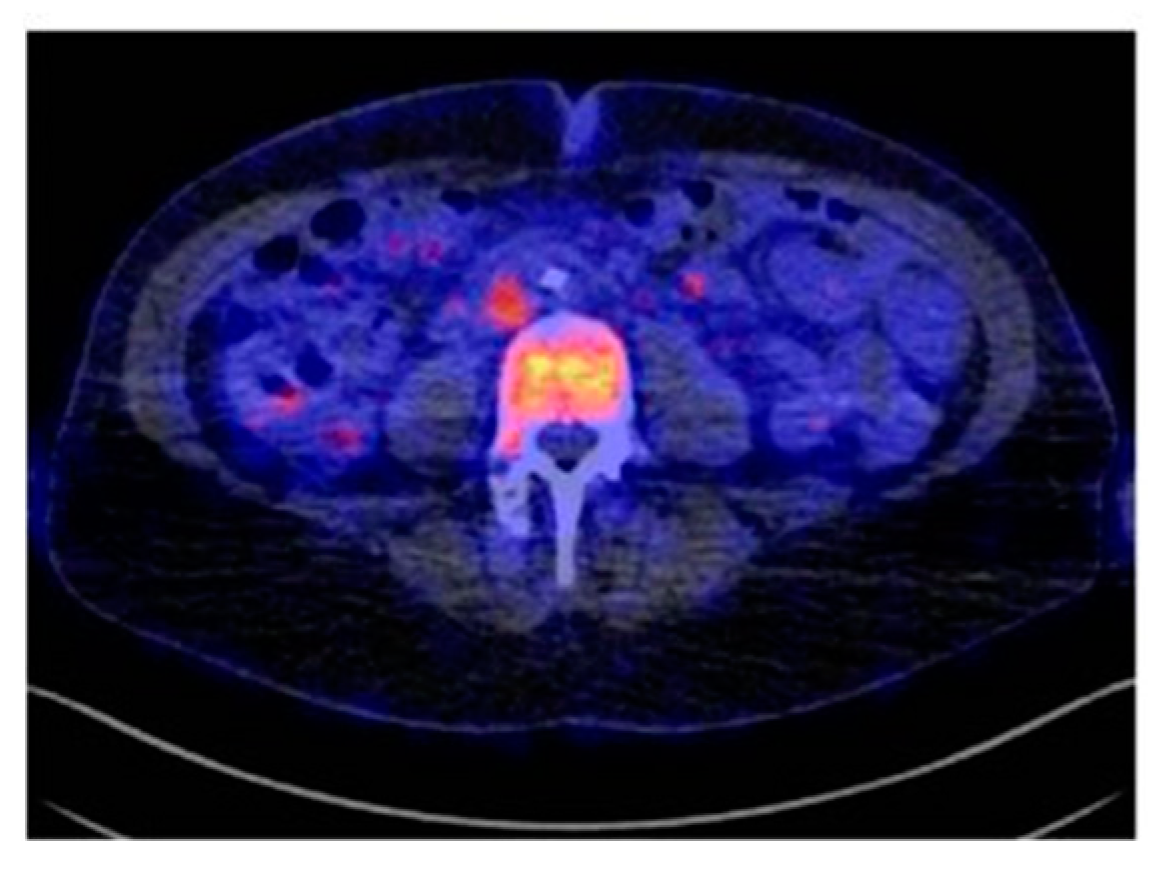

- Bensch, F.; van der Veen, E.L.; Lub-de Hooge, M.N.; Jorritsma-Smit, A.; Boellaard, R.; Kok, I.C.; Oosting, S.F.; Schröder, C.P.; Hiltermann, T.J.N.; van der Wekken, A.J.; et al. 89Zr-atezolizumab imaging as a non-invasive approach to assess clinical response to PD-L1 blockade in cancer. Nat. Med. 2018, 24, 1852–1858. [Google Scholar] [CrossRef]